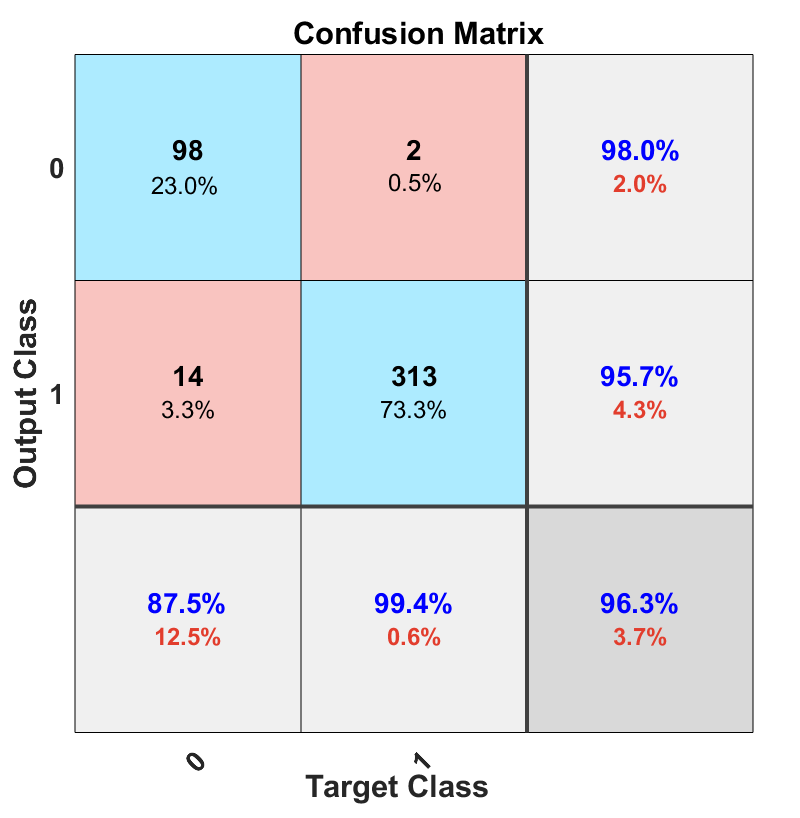

Fig. 2 shows the confusion matrices of leave-one-out quadratic SVM with augmentation on the right side versus no augmentation on the left side. By applying the augmentation method, not only did the total accuracy increase slightly to 97.2% but also the false negative (folded patch, but classified as normal patch) also decreased from 2.6% to 2.1%. However, the false positive (normal patch, but classified as a folded patch) remained unchanged. In general, any type of error is not desirable, nevertheless, in our case, false positive might be preferred over false negative.

[5pt] \stackunder[5pt]

\stackunder[5pt]